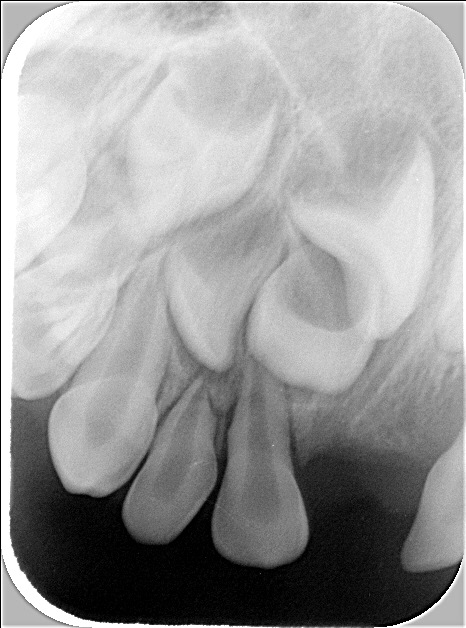

Röntgenbild 2

Dieses Röntgenbild wurde von mehr rechts seitlich aufgenommen und erstellt, um den möglichen überzähligen Zahn 12' darzustellen, den man auf dem ersten Bild vermutet hat. Beim 52' kann eine Fraktur (ein Bruch) der Wurzelspitze vermutet werden, oder wahrscheinlicher, eine weitere überzählige Zahnstruktur. Dieser Befund wird zu einem späteren Zeitpunkt wieder beurteilt; er bedarf momentan keiner Therapie.

Röntgenbild 2 der Oberkiefer-Front (mehr seitlich von rechts aufgenommen, um den überzähligen Zahn 12' darzustellen)